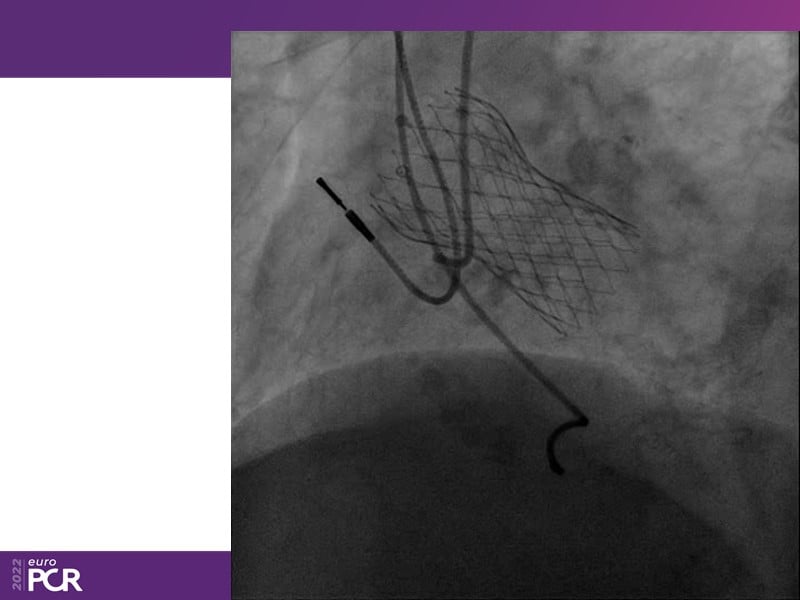

Consult this session to learn how to contribute to streamlined pre- and post-TAVI patient pathways, to discover updates on the optimised TAVI procedure and appreciate the variances in different valve designs and the long-term patient outcomes, as well as to discuss the right time of PCI in TAVI patients (steps on the procedure).

- To discuss the right time of PCI in TAVI patients (steps on the procedure)